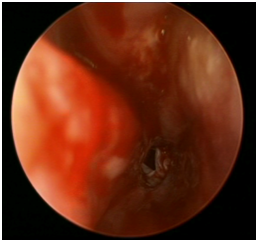

In this technique, the surgeon introduces a 2.9mm endoscope through the nasal cavity. Identification of choanal atresia is then performed. Using a straight suction, a puncture is performed anterior-inferiorly close to the vomer bone of the nasal septum (Figure 2A). Visualization of adenoid pad in the nasopharynx assures proper puncture through atresic palte and not into soft palate (false passage). The opening is then enlarged using a drill or shaver depending on the thickness of the atretic plate (Figure 2B, Figure 2C). A mucosal flap is usually not possible to preserve by the end of the procedure. The other choana atresia side is addressed similarly. Lastly, the vomer is removed using a backbiter forceps. Two size 3.5 endotracheal tubes are used one in each side and tied together anteriorly using a sub-labial suture for fixation to avoid collumellar pressure. The stent are removed in the clinic six weeks later.

A                                                                      B                                                            C

Figure 2 A) Transnasal endoscopic puncture using a straight suction for right choanal atresia. B) Shaver blade enlarging the puncture opening. C) Final result.